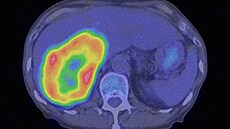

Pokud operace není možná, využívají se metody, které ničí nádorové buňky cíleně — například radiofrekvenční ablace nebo chemoembolizace, kdy se nádor „přidusí“ tím, že se uzavřou cévy, které ho vyživují. U pokročilých stadií se používá systémová léčba, která může průběh onemocnění zpomalit, i když jej už nedokáže zcela vyléčit.